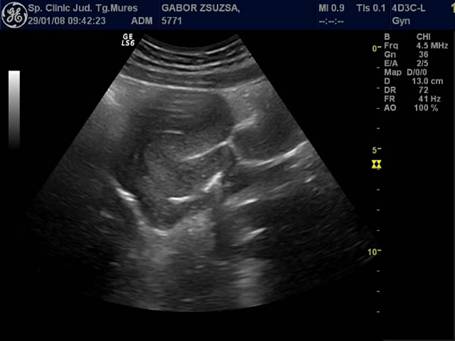

Uterul - situat intre vezica si rect, pozitia lui poate fi variabila, influentata si de umplerea vezici. De obicei, corpul uterin si colul au o relativa omogenitate interna ecografica. Cateodata imagini anecogene in peretele cervical reprezinta chiste Naboth.

Dimensiunile uterului la o pacienta nulipara matura, masurate transvaginal sunt de 7,3 cm x 4,0 cm x 3,2 cm. In general dimensiunile cresc cu paritatea si scad dupa menopauza.

Raportul intre corp si col este aproximativ de 1,6 in ceea ce priveste lungimea.[5,6]

Fig. Nr.358. Uter in sectiune longitudinala, in anteversoflexie

Fig. Nr.359. Sectiune transversala la ecografia transvaginala, la nivelul corpului uterin